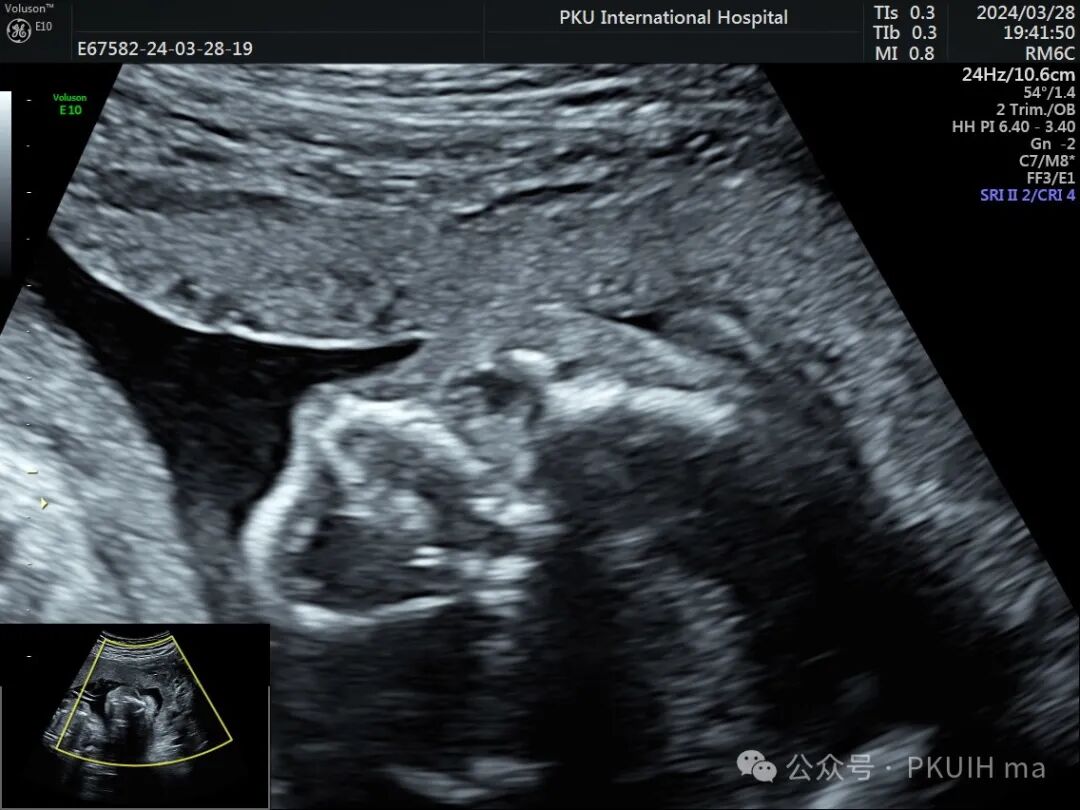

双眼球对比观察两眼球发育不对称,右眼明显发育小

右眼球情况:两个手标分别代表晶状体和后方的永存玻璃体

实时动态观察双眼发育不对称,右眼小;两侧眼球内晶状体、玻璃体均可见,右侧晶状体小,晶状体后缘玻璃体内见不规则的高回声区。

PHPV的超声表现:一侧眼球晶状体后方可见Y形高回声或强回声条带,或者是晶状体后方圆形或圆弧状高回声团块(直接征象);同时伴有患侧眼球小,晶状体形态异常,眼轴短,部分有玻璃体浑浊。双眼发病极为罕见,表现双层晶状体浑浊,内见不规则强回声或高回声带。CDFI:部分病例可见增生的玻璃体动脉内见血流信号。该病容易反复发生眼内出血,纤维血管性肿块的收缩可能对视网膜产生牵拉,导致视网膜脱离。因此,眼部超声表现可能会随着妊娠进展而改变。